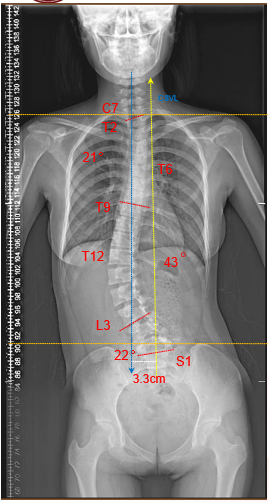

影像顯示患者側彎度數已經超過40度

經過影像學檢查,中山六院脊柱外科陳克冰主任醫師表示,「側彎度數已經超過40度!需要通過手術治療矯正,防止畸形進一步加重。」